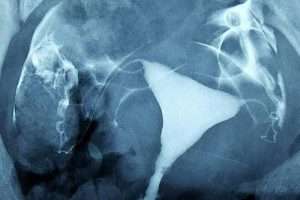

İki Taraflı Salpenjitis Istmica Nodosa (SIN) ve Hidrosalpinks